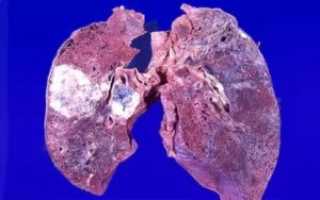

Низкодифференцированная аденокарцинома легких – одна из наиболее злокачественных видов опухолей. При развитии указанного патпроцесса наблюдается сильное разрастание стромы, и модификация тканей, образовавших тот или иной орган. Такие новообразования высокоактивны.

Уже на начальных стадиях своего генеза дают метастазы. Умеренно дифференцированная аденокарцинома легкого не имеет четко выраженных границ, состоит из атипичных клеток.

Бронхопульмональный железистый рак легких чаще всего выявляют в организме женщин. Опухоль высокоактивна, образует множественные метастазы. Этот вид канцера следует отличать от нейроэндокринного рака, альвеолярной аденомы, реактивных метапластических модификаций эпителия, склерозирующей гемангиомы, метастатических поражений, бронхоальвеолярной аденомы, атипичного карциноида.